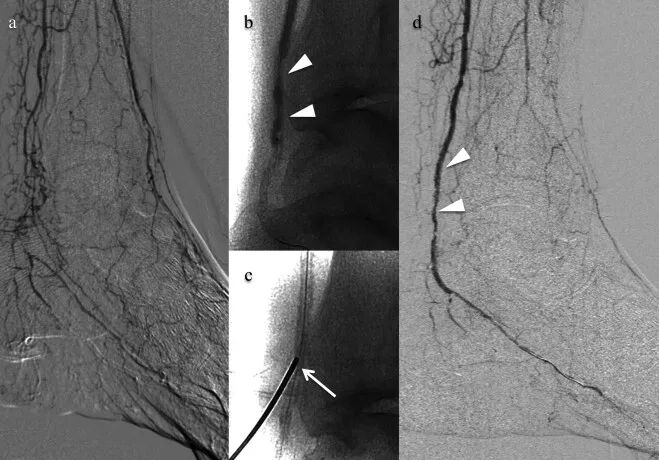

经皮直接穿刺股浅动脉或胫动脉钙化斑块以辅助球囊导管通过及钙化病变球囊扩张的技术。

通讯作者单位:奈良县立医科大学

a、b. 内PIERCE技术示意图。图a显示,通过建立顺行入路部位与远端穿刺部位之间的导丝外置化,或通过顺行球囊导管在钙化病变近端锚定逆行导丝,实施远端BTK或BTA穿刺的双向入路。图b显示,从远端穿刺部位沿导丝将20G穿刺针置入动脉内,小心地边旋转边推进20G穿刺针,数次穿过钙化病变。

动脉钳怎么用动脉重度钙化导丝无法通过 针具技术超补救策略_https://www.jmylbn.com_新闻资讯_第19张

a–f. 器械输送困难的代表性病例。术前血管造影(a)显示胫后动脉(PTA)长段慢性完全闭塞(CTO)。图b显示,从PTA远端的逆行导丝穿过CTO病变并被外置化。低剖面球囊导管无法穿过钙化病变(虚线)。图c显示内PIERCE技术。图d显示低剖面球囊穿过并扩张钙化病变。图e显示通过长球囊导管实现充分的病变扩张。最终血管造影(f)显示PTA成功重建血运。